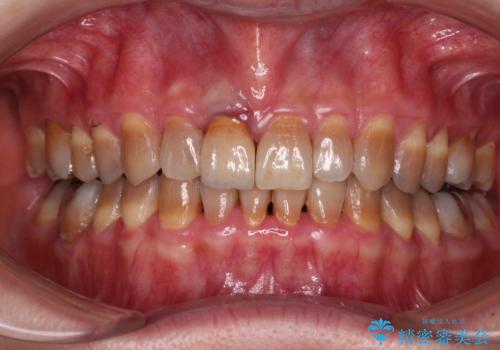

前歯が折れたついでに歯並びも改善 矯正治療と前歯のセラミック治療